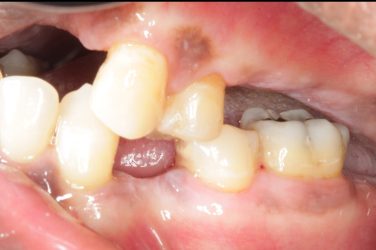

This patient wants implants. We just finished treating her periodontal disease and she is ready for the next phase, however, she has severe bite collapse. In addition, she has uneven ridge in the upper anterior, which would make it challenging esthetically. I asked her dentist to make her a partial denture but the patient kept going back…